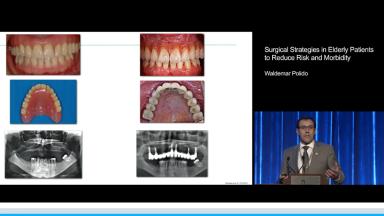

Surgical Strategies in Elderly Patients to Reduce Risk and Morbidity

This lecture outlines implant strategies in elderly patients that aim to achieve three objectives: reduce risk and morbidity, maintain predictability, and allow maintenance and retrievability. Waldemar Polido presents key points of treatment planning, appropriate preoperative care, and surgery specific to the elderly patient. He addresses the role of digital planning and guided surgery in these patients. He also details the surgical and restorative options in accordance with his three objectives for a variety of clinical situations - single missing tooth, partial edentulism, and complete edentulism. Multiple clinical cases are presented to show the concepts of using shorter implants to avoid major grafting, restoring the dental arch only to premolars or first molars, and using screw-retained prostheses to allow retrievability.

- ITI Annual Conference 2015 - Istanbul, Turkey